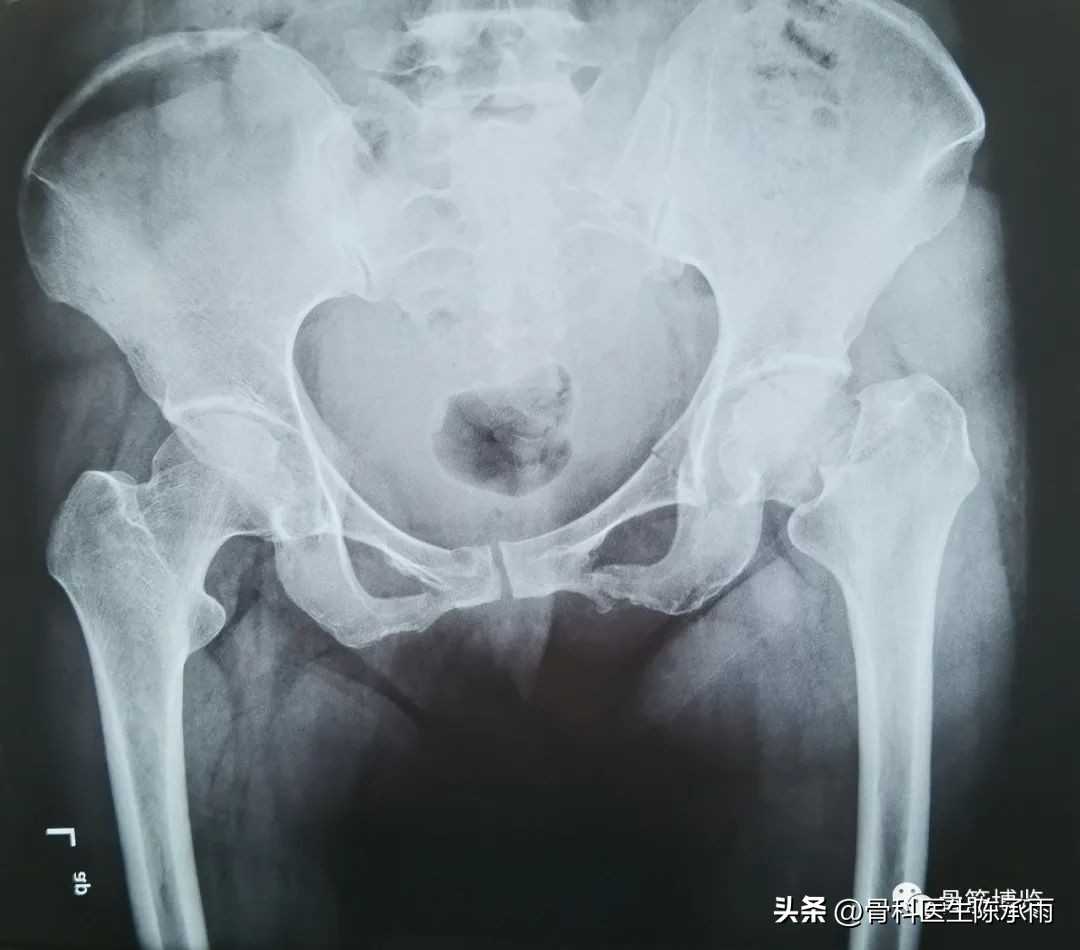

1例

常规股骨颈骨折相对简单